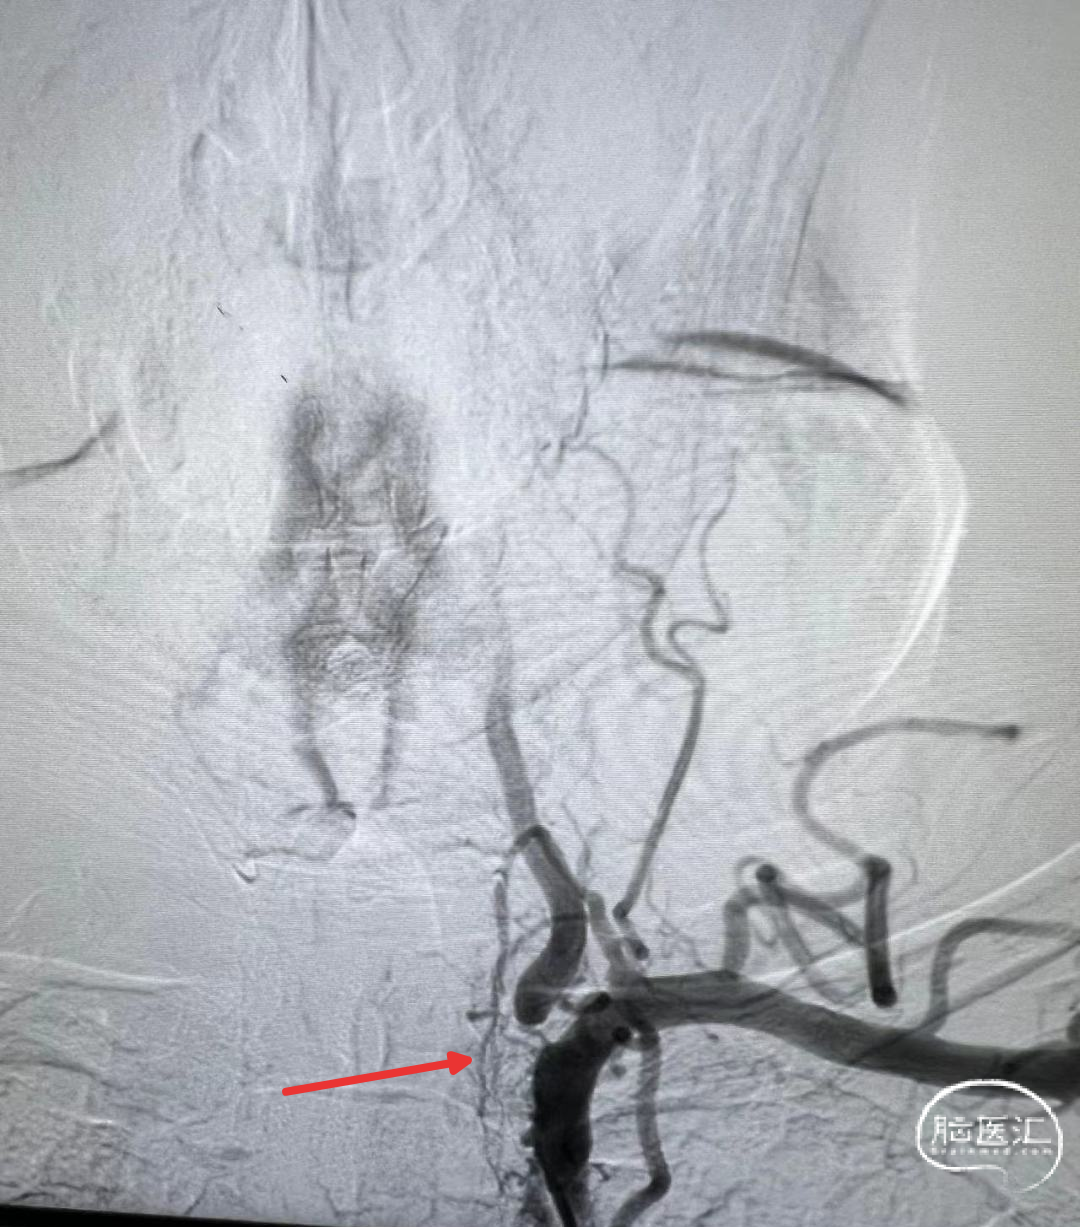

术前DSA影像

右侧颈内动脉起始部中度狭窄,未见血流向后循环代偿。

左侧颈内动脉造影提示后交通开放,代偿供应后循环。

左侧椎动脉开口重度狭窄,前向血流缓慢,V4闭塞。